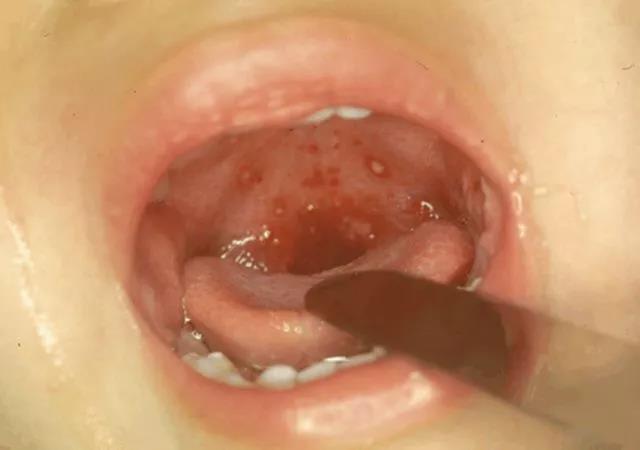

以上這些是3種最易混淆的小兒傳染病,分別為:手足口病、皰疹性咽峽炎、玫瑰疹(幼兒急疹)。